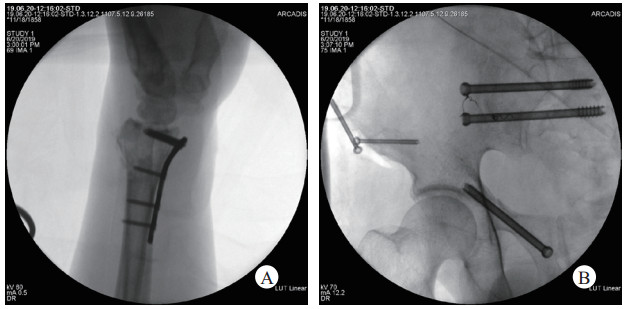

1.4.56月20日经骨科讨论, 拟定手术方案:全麻下行“天玑机器人辅助下骨盆环多发骨折骶髂通道螺钉固定术+髋臼前柱通道螺钉固术; 右侧髂前下棘骨折切开复位通道螺钉内固定术(图 6A); 左桡骨远端骨折切开复位内固定术(图 6B)”[8]。术后患者再入监护室复苏治疗。

| 图 6 A骨盆环内固定;B左桡骨远端骨折切开复位内固定 |